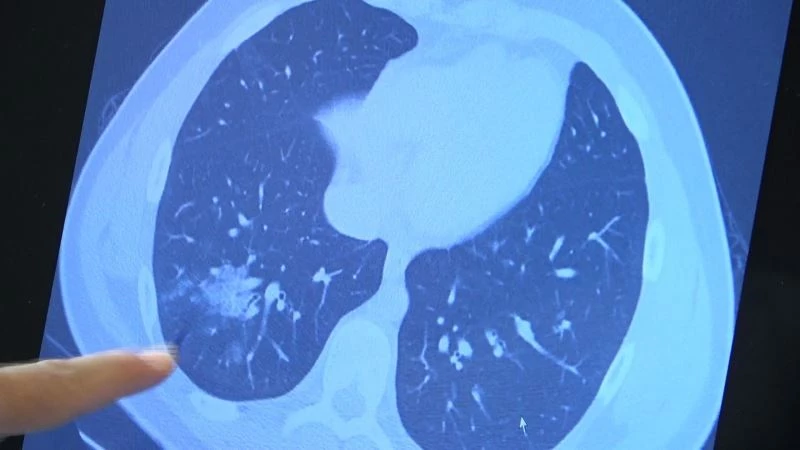

Korona virüste aşılama yaşı her geçen gün düşerken aşı olmayan çocuklarda da ciddi akciğer tutulumları görülmeye başladı. 12 yaş üzeri kronik rahatsızlığı olan hastalara artık aşılama yapılabiliyor. Göğüs Hastalıkları Uzm. Prof. Dr. Şevket Özkaya ise aşı olmamış kronik rahatsızlığı olan 14 yaşındaki bir çocuğun akciğerlerinde oluşan ciddi tahribatı gözler önüne serdi.

Bazı vatandaşlar hâlâ aşı olmakta tereddüt etmeye devam ederken korona virüs çocuk grubundaki hastaları da etkilemeye başladı. VM Medical Park Samsun Hastanesi Göğüs Hastalıkları Kliniği’nden Prof. Dr. Şevket Özkaya ise aşı olabilecek yaş grubundaki çocukların bir an önce aşılanması gerektiğine vurgu yaptı. 14 yaşında, kronik rahatsızlığı olan ve akciğerlerinde tahribattan dolayı ciddi öksürük, ateş ve nefes darlığı çeken bir hastanın akciğerlerini inceleyen Prof. Dr. Özkaya, "14 yaşındaki kronik rahatsızlığı mevcut olan bir genç hastamızda ciddi akciğer tutulumları var. Her iki akciğerinde de yaygın buzlu cam ve konsolidasyon alanları var. Bu yaştaki çocuklarda beklemediğimiz bir durumdur. Okullarımızda da bu risk var. Okullarımızın açık kalmasının ve sağlık sistemimizin kitlenmemesi için mutlaka aşı olmalıyız. Çocuklarımıza rol model olmalıyız. Şu anda hastanelerimiz hastalara yetişebiliyor. Yatak sayımız yeterli. Ancak kontrollü sosyal hayatımızı düzene sokmadıkça ve aşı olmadıkça, gelecekte hastanelerde yatak sayısı sıkıntısı çekebiliriz" dedi.